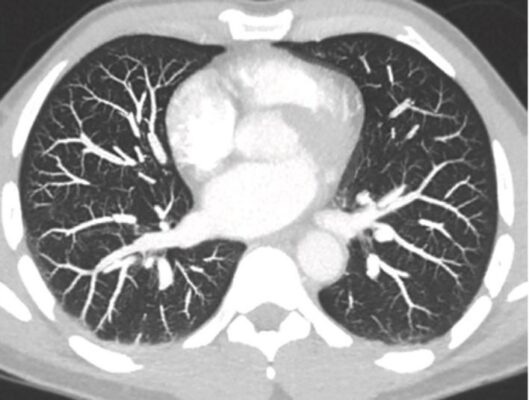

- Chụp CT ngực thường được “chia cửa sổ” và được hiển thị ở ít nhất hai định dạng nhằm xác định giải phẫu một cách tối ưu.

- Các cửa sổ phổi (Lung windows) được chọn để lấy hình ảnh rõ nhất các bất thường của nhu mô phổi và xác định giải phẫu phế quản bình thường và bất thường. Các cấu trúc trung thất thường xuất hiện dưới dạng một đậm độ trắng đồng nhất trên các cửa sổ phổi.

- Các cửa sổ trung thất (Mediastinal windows) được chọn để hiển thị các cấu trúc trung thất, rốn phổi và màng phổi. Phổi thường có hình ảnh đen hoàn toàn khi nhìn với cửa sổ trung thất.

GIẢI PHẪU CT BÌNH THƯỜNG CỦA PHỔI

- Tất cả các giải phẫu có thể nhìn thấy trên phim X quang ngực thông thường đều quan sát được trên phim chụp CT ngực, nhưng với độ chi tiết hơn. Với việc tái tạo các hình ảnh CT lát cắt mỏng, phổi có thể được hình dung ở bất kỳ mặt phẳng nào, mặc dù ba mặt phẳng phổ biến nhất là mặt phẳng ngang (axial), mặt phẳng đứng dọc (sagittal) và mặt phẳng trán (coronal, còn gọi là mặt phẳng vành) (Hình 11).

- Các mạch máu: Có thể nhìn thấy gần như toàn bộ đường đi của chúng từ rốn phổi đến bề mặt màng phổi. Có thể phân biệt các động mạch phổi với các tĩnh mạch phổi (Hình 12).